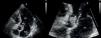

Caso clínicoDoente do género masculino, de 50 anos de idade, com antecedentes médicos de tabagismo, toxicodependência e hepatite C crónica, recorreu ao serviço de urgência por astenia, febre e cefaleia com um mês de evolução e dor abdominal desde há 2 dias. Ao exame objetivo o doente apresentava febre e a auscultação cardíaca evidenciou um sopro diastólico agudo, em decrescendo, grau iii/vi, ao nível do bordo esquerdo do esterno. O doente não apresentava sinais de insuficiência cardíaca. O estudo analítico demonstrou insuficiência renal aguda (Cr 2,5mg/dl, Ureia 60mg/dl, valores normais em análises efetuadas uma semana antes), elevação da proteína c-reativa (77,5mg/L) e anemia normocítica e normocrómica (Hb 11,2g/dl). Realizou tomografia computorizada (TC) abdominal que evidenciou esplenomegalia, não se visualizando áreas de enfarte, e hidroureteronefrose direita condicionada por aneurisma da artéria ilíaca comum direita com 42mm de maior diâmetro. Efetuado ecocardiograma transtorácico no qual se observou uma vegetação de 15mm na cúspide não coronariana da válvula aórtica (Figura 1) e insuficiência aórtica severa (Figura 2), com compromisso moderado a grave da função sistólica do ventrículo esquerdo (fração de ejeção de 35%), achados confirmados por ecocardiograma transesofágico. O doente foi internado no Serviço de Cardiologia, tendo iniciado antibioterapia empírica com vancomicina e meropenem. Foi decidido não introduzir aminoglicosídeo atendendo à taxa de filtração glomerular baixa, estimada em 20ml/min/1,73m2. No 2.° dia de internamento verificou-se lentificação cognitiva do doente, sem alterações neurológicas focais, tendo-se requisitado ressonância magnética (RM) cerebral, na qual foi possível observar múltiplos enfartes cerebrais recentes. As hemoculturas isolaram Candida albicans (C. albicans) sensível à anfotericina lipossómica, tendo-se iniciado terapêutica antifúngica e contactado o centro cirúrgico no sentido de transferir o doente para substituição valvular aórtica. Enquanto aguardava transferência, o doente iniciou dor súbita intensa no membro inferior esquerdo, com arrefecimento e perda de pulsos, constituindo um quadro de isquemia aguda do membro, de provável causa cardioembólica (vegetação micótica). Foi transferido para o centro de cirurgia vascular com urgência, onde realizou tromboembolectomia arterial femuro-distal esquerda. Posteriormente foi transferido para o centro de cirurgia cardiotorácica onde se procedeu à substituição da válvula aórtica por prótese biológica. O exame microbiológico da válvula aórtica e do êmbolo retirado da artéria femoral esquerda demonstraram crescimento de C. albicans. O ecocardiograma transtorácico pós-operatório evidenciou prótese aórtica normofuncionante, tendo sido transferido para o Serviço de Cardiologia deste hospital 14 dias depois. Durante o internamento apresentou febre e subida dos marcadores de inflamação. Repetiu o ecocardiograma transtorácico que confirmou a presença de prótese normofuncionante, sem evidência de vegetações. Realizou angio-ressonância magnética abdominal e dos membros inferiores, tendo sido identificado: volumoso pseudoaneurisma do eixo arterial ilíaco direito com oclusão da artéria ilíaca externa distal ao pseudoaneurisma; múltiplas tumefações compatíveis com abcessos na região inguinal e coxa esquerdas (local da abordagem cirúrgica vascular prévia); e abecedação do compartimento muscular ântero-lateral da perna esquerda (Figura 3). Atendendo à existência de foco infeccioso e ao ecocardiograma transtorácico sem evidência de endocardite, decidiu-se não repetir o ecocardiograma transesofágico. O paciente foi transferido para o Serviço de Cirurgia Vascular, tendo sido submetido a tratamento cirúrgico: aneurismectomia total com realização de pontagem femuro-femoral cruzada esquerda-direita com veia grande safena direita invertida, associado a exploração e drenagem dos abcessos na coxa e na perna esquerdas. O exame microbiológico do pseudoaneurisma evidenciou crescimento de Staphylococcus epidermidis (S. epidermidis). Durante o internamento no Serviço de Cirurgia Vascular o doente manteve febre intermitente e deterioração progressiva do estado geral. Repetiu hemoculturas que demonstraram crescimento de S. epidermidis, tendo iniciado antibioterapia de largo espectro com vancomicina e meropenem. Realizou TC pélvico e das coxas identificando-se 2 novos pseudoaneurismas: na artéria ilíaca interna esquerda e na artéria femoral superficial esquerda. O paciente foi novamente submetido a tratamento cirúrgico: durante o procedimento constatou-se a rápida progressão da situação clínica, havendo rotura do pseudoaneurisma femoral esquerdo, com extensa infiltração hemorrágica e abcedação da coxa. Procedeu-se a laqueação das artérias ilíaca interna esquerda e femoral superficial esquerda, associado a desbridamento alargado de tecidos desvitalizados e de coleções purulentas. Em tempo cirúrgico deferido procedeu-se a amputação transfemoral aberta, por ter havido progressão para gangrena da perna. Durante o internamento prolongado no Serviço de Cirurgia Vascular, de cerca de 4 meses, o doente manteve sempre terapêutica antifúngica e foi submetido a reamputação transfemoral e a vários desbridamentos cirúrgicos de abcessos do coto. Após o encerramento parcial do coto o doente obteve alta, clinicamente estável, tendo-se decidido não manter antifúngico devido à hepatite C crónica que o doente apresentava e à possível toxicidade hepática dos antifúngicos.